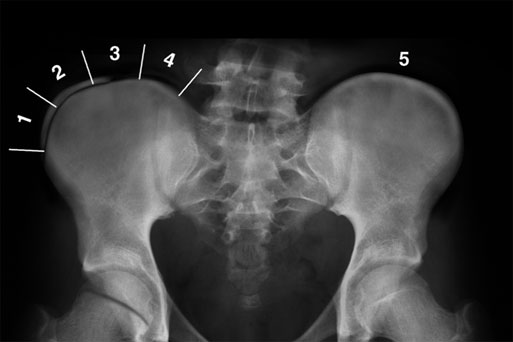

방사선에서도 쉽게 관측할 수 있는 것이 바로 장골골단 입니다.

각 단계마다 확인해보면 1단계는 25% 이하, 2단계는 25~50%, 3단계는 50~75%, 4단계는 75~100% 골화가 진행되는 것으로 분류하고, 5단계는 장골에 유합되는 것입니다.

아래는 Risser 4 사진임을 유추해 볼 수 있습니다. 척추의 성장이 거의 끝난 상태인 것이지요.